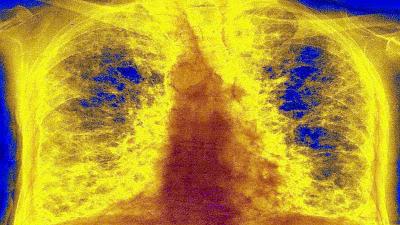

कोरोनामुळे होणाऱ्या या आजाराचे नाव लंग फायब्रोसिस आहे. त्याला पल्मोनरी फायब्रोसिस देखील म्हणतात. यासंबंधीचा एक लेख लंग इंडिया नावाच्या वैद्यकीय जर्नलमध्ये प्रसिद्ध झाला आहे.

केवळ ५ टक्के लोक असे आहेत ज्यांना तीव्र श्वसनाचा त्रास सिंड्रोम (ARDS) नावाचा आजार आहे. याचा अर्थ असा आहे की, केवळ ५ ते १० टक्के लोक लंग फायब्रोसिसची (Lung Fibrosis) तक्रार करीत आहेत.

लंग फायब्रोसिस या रोगात फुफ्फुसातील ऊतक म्हणजेच टिश्यू (Tissue) सूजण्यास सुरुवात होते. यामुळे फुफ्फुसांच्या आतल्या हवेची जागा कमी होऊ लागते. याचा परिणाम म्हणजे श्वास घेण्यात अडचण होते. यामुळे एखाद्या व्यक्तीला थकवा जाणवतो. जर परिस्थिती अधिक गंभीर झाली तर रुग्णाचा मृत्यूही होऊ शकतो किंवा त्याला हृदयविकाराचा झटका येऊ शकतो.

याचबरोबर, डॉ. उदवागिया यांनी सांगितले की, काही रुग्णांना बरे झाल्यानंतरही त्यांच्या घरी ऑक्सिजनची आवश्यकता असते. जेव्हा रुग्ण बरे झाल्यानंतर तीन महिन्यांनंतर सीटी स्कॅन केला जातो, तेव्हा त्यांच्या फुफ्फुसांची अवस्था अत्यंत खराब असल्याचे निदर्शनास आले आहे. तीन दशकांपूर्वी लंग फायब्रोसिस रोग सहसा फारच कमी लोकांना होता. ज्यास्तकरून हा रोज वयस्कर लोकांना होता.

डॉ. उदवागिया म्हणतात की, मला आशा आहे की बहुतेक लोक फुफ्फुसातील रोग पासून बरे होऊ शकतात. परंतु काही लोकांमध्ये हा आजार घर करून बसेल. जर लंग फायब्रोसिस दीर्घकाळापर्यंत एखाद्या रूग्णात राहिला तर त्याला श्वसनसंस्थेशी संबंधित दीर्घकाळ आजार असू शकतात किंवा तो कायमच फुफ्फुसांच्या आजाराने ग्रस्त असू शकतो. या रोगाचा सर्वात मोठा इलाज म्हणजे बचाव.